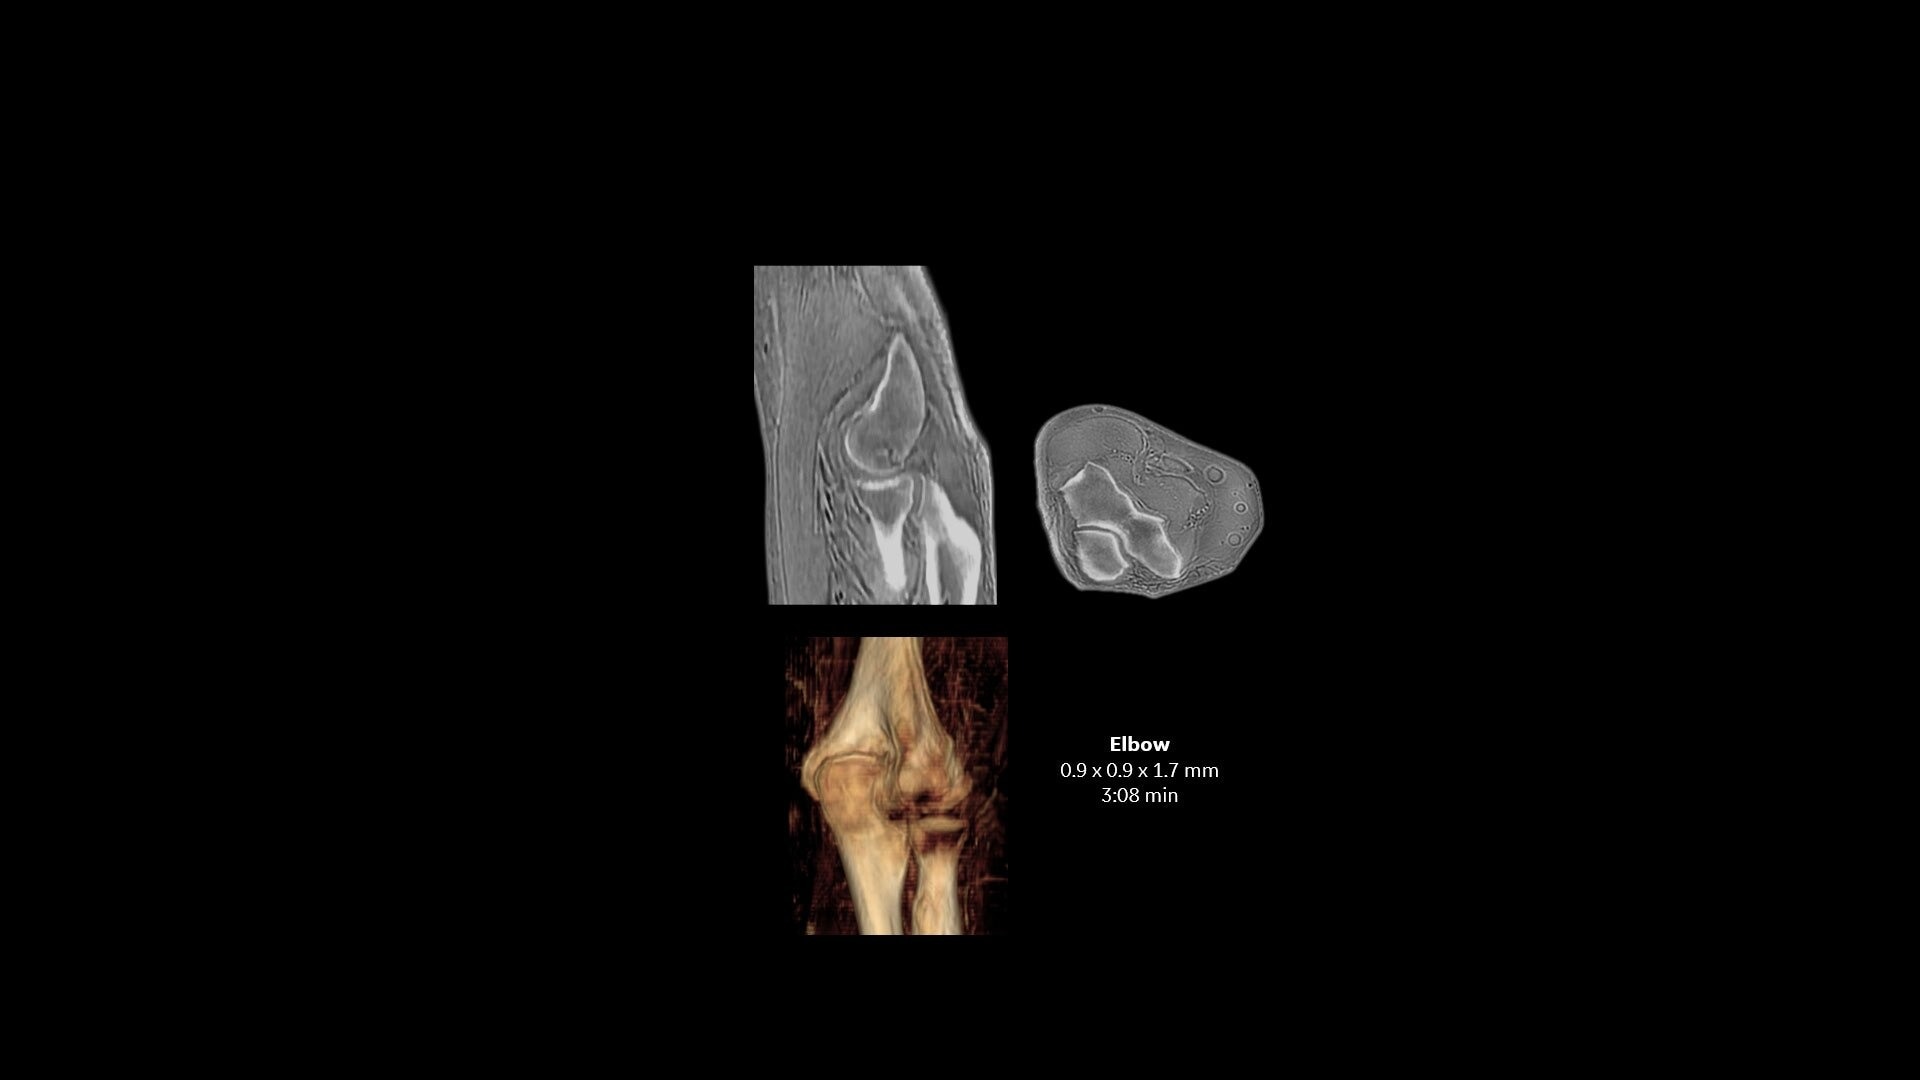

One-stop Orthopedic Shop

Provides cortical bone information co-registered with the soft tissue series

Ease Patient Burden

Help eliminate separate imaging modality appointments, potentially reduce healthcare costs